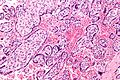

English: Very high magnification micrograph of maternal malaria. Placenta. H&E stain.

The images show organisms within the red blood cells. Related images

Red blood cell infected by malaria.

Red blood cell infected by malaria.